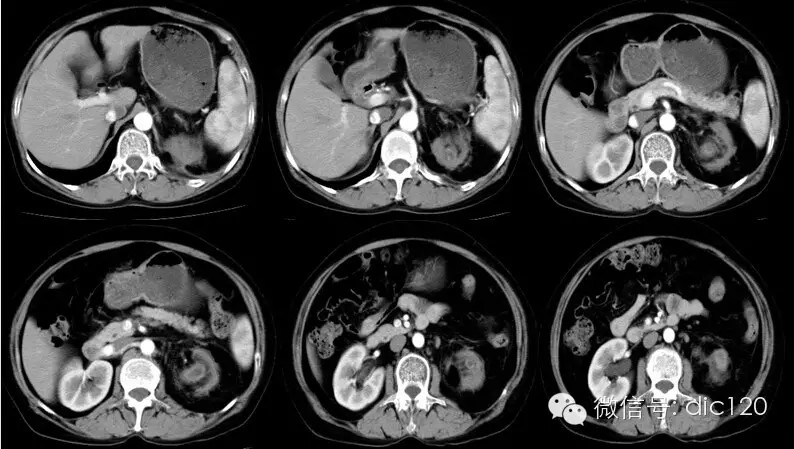

影像表现:CT平扫左肾体积变小,肾皮质变薄,肾盂扩张、壁增厚,见小点状高密度影,肾盏扩张,增强扫描病变周围组织呈环形强化,囊变区不强化,肾周模糊,筋膜增厚,临近腹膜增厚,左侧输尿管近段见结节状高密度结石影。 分析:1、中年妇女,左上腹不适;2、肾盂肾盏扩张、壁增厚,增强环形强化;3、输尿管及肾盂小结石;4、肾周筋膜增厚。 符合肾脏感染性病变,考虑黄色肉芽肿型肾盂肾炎。 |